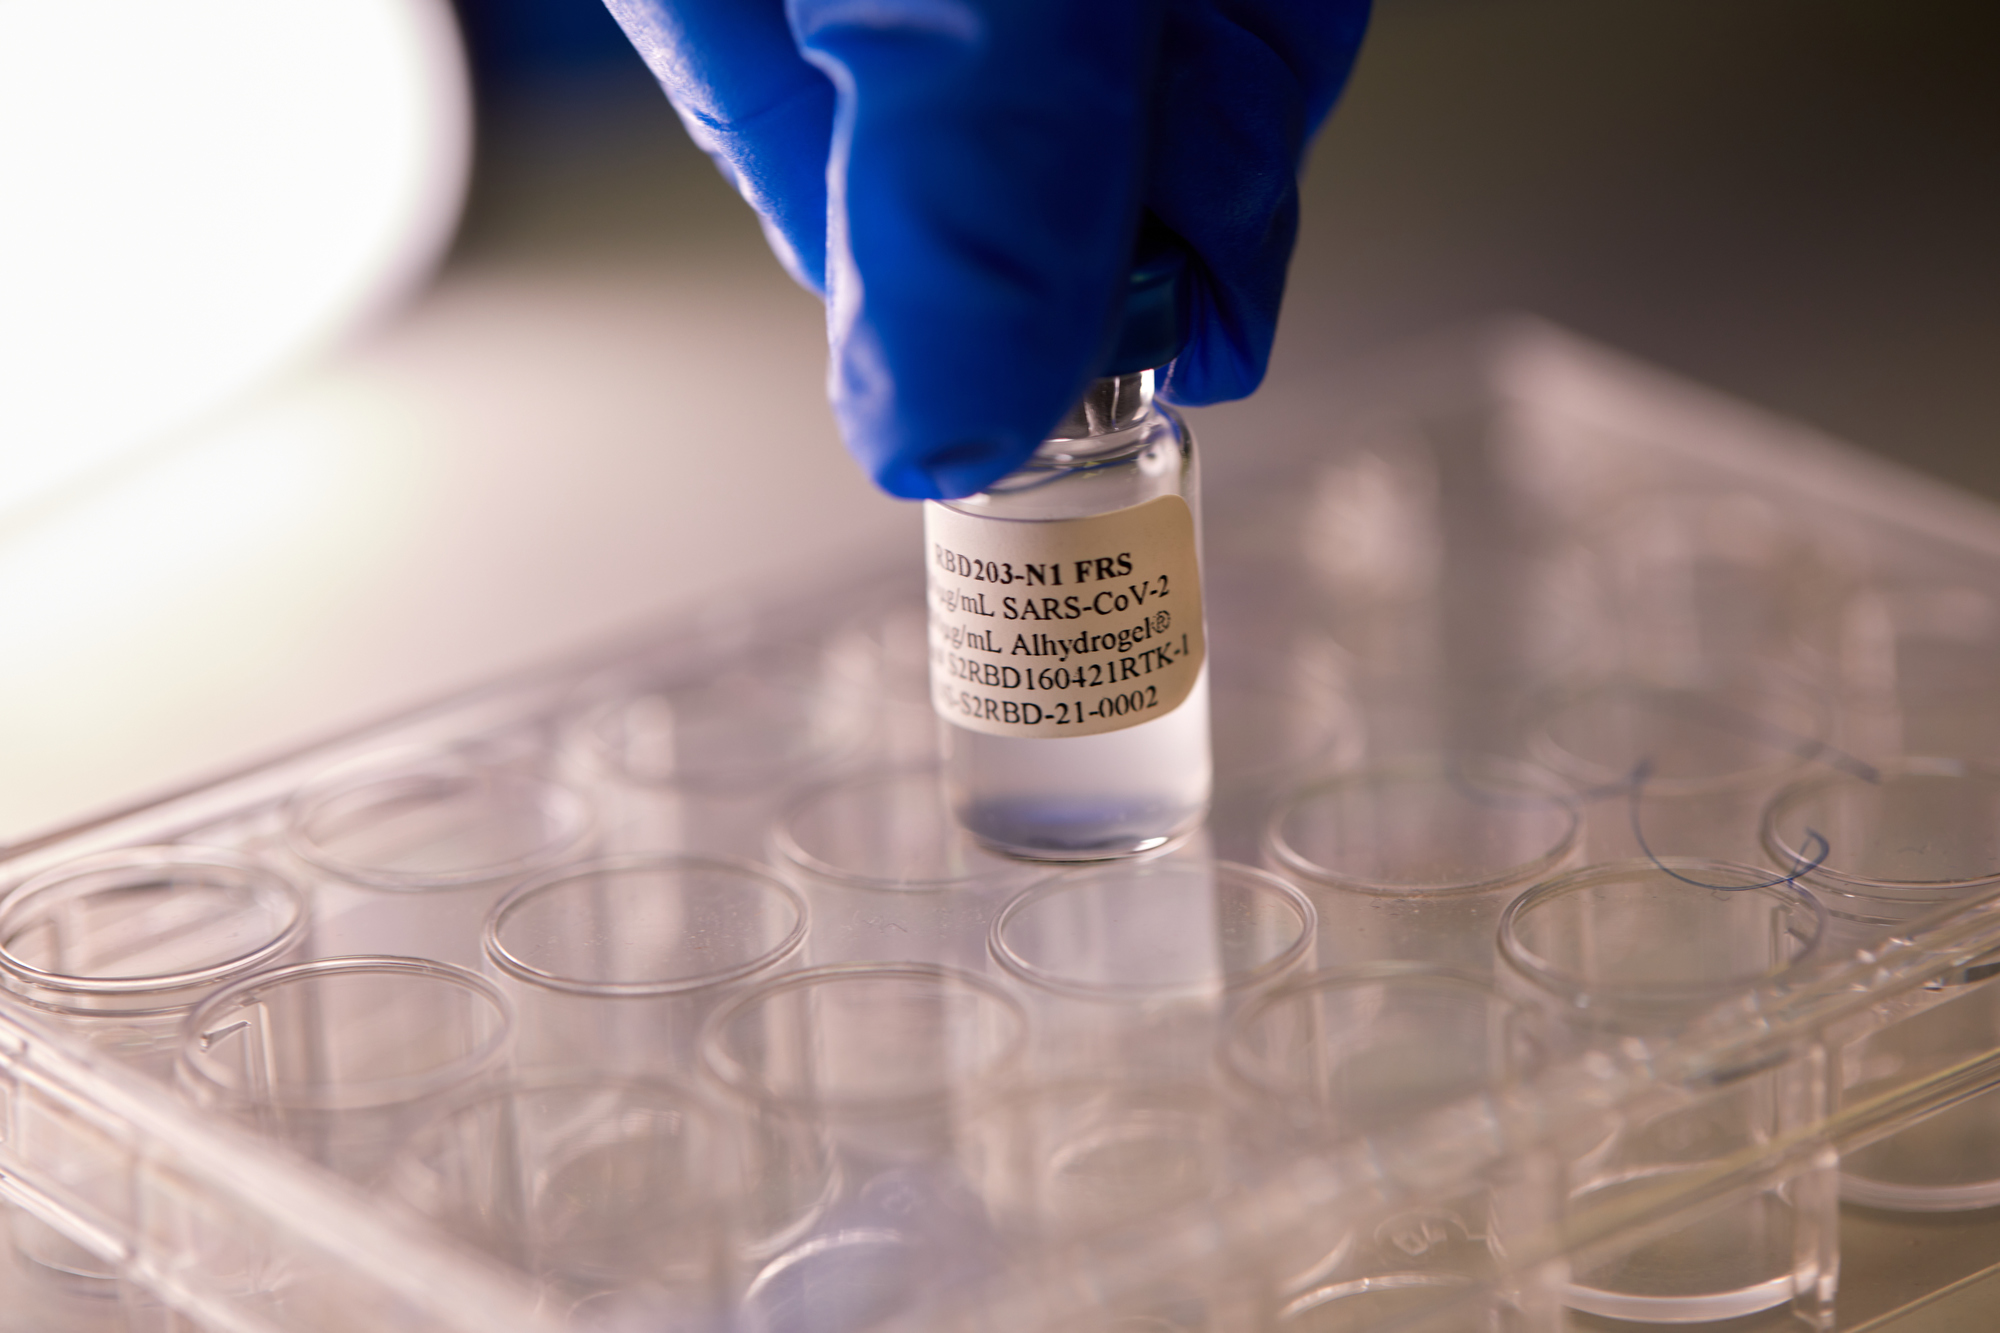

Coronaviruses

Covid-19, SARS, MERS